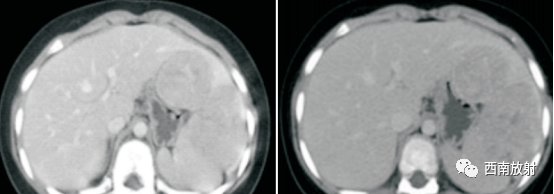

▲病例1:肝母细胞瘤:CT平扫显示肝左叶S2/3类圆形稍低密度肿块,边界模糊,增强扫描动脉期病灶显示不均匀强化、以边缘强化为主并见增粗的肝左动脉供血,门脉期及延迟期病灶强化逐渐减退。(病例来源:李钱程.儿童肝母细胞瘤的 CT诊断中表现及误诊分析[J].中国CT和MRI杂志,2020.18(11):107-109.)